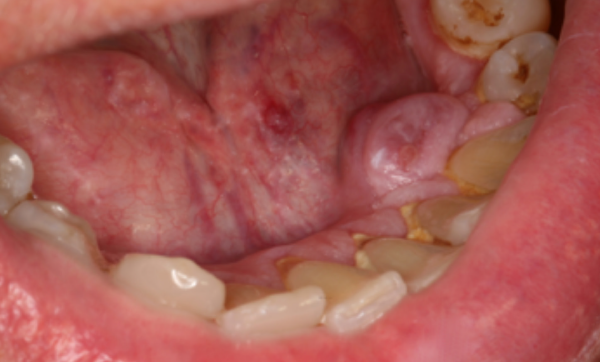

Examen clinique. On observait une tumeur gingivale indolore, sessile, hémisphérique, de 1 cm de diamètre et 0,5 cm d’épaisseur, siégeant sur le versant lingual, à hauteur de la 33. Elle avait une consistance très dure qui, dans un premier temps, a fait évoquer une exostose ; l’absence de résistance à la pénétration de l’aiguille a permis d’éliminer ce diagnostic. La tumeur avait une surface régulière et, lors de sa croissance, elle avait perdu sa couleur homogène. Elle était alors recouverte par une muqueuse rose comportant des plages rouge violacé. Par ailleurs, certaines papilles interdentaires étaient légèrement hyperplasiques, séquelle probable du traitement par la ciclosporine.